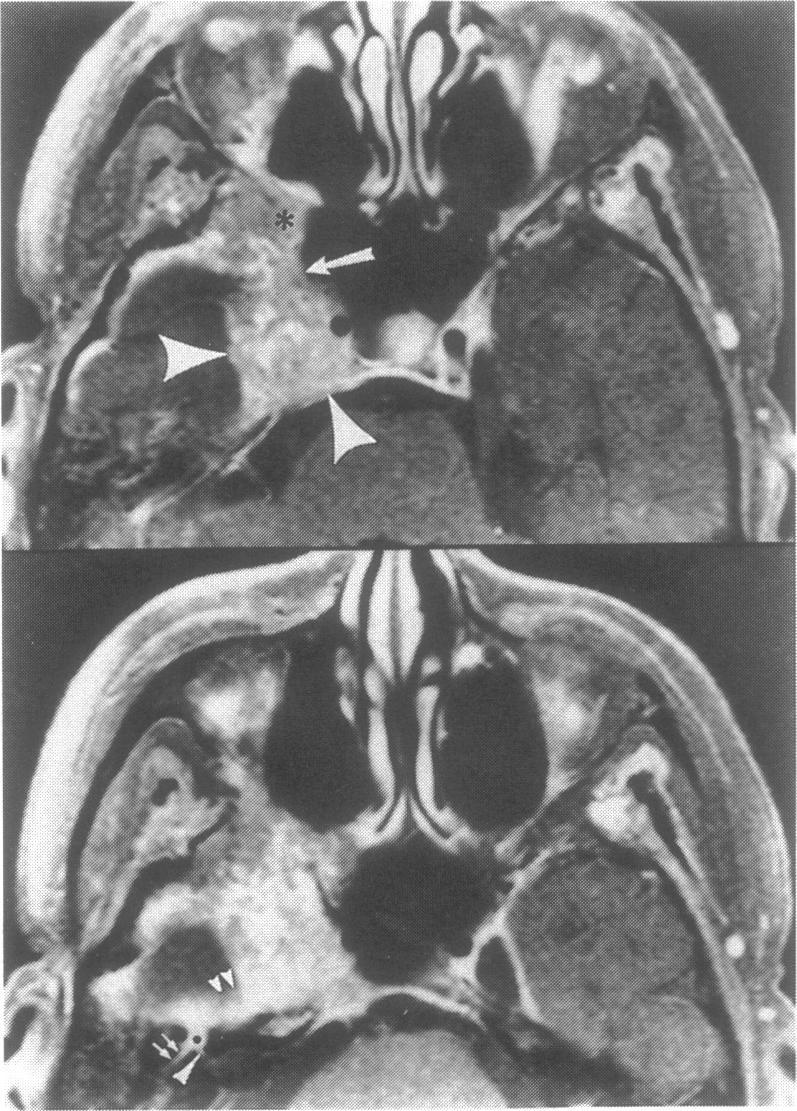

Adenoid cystic carcinoma of the hard or soft palate is a slow-growing, insidious disease with a tendency to spread via a perineural mechanism along the palatine branches of the maxillary division of the trigeminal nerve. Such spread may present first as a tumor in the pterygopalatine fossa or cavernous sinus. The purpose of this manuscript is to report three cases of palatal adenoid cystic carcinoma which presented as a mass in the cavernous sinus prior to discovery of the palate primary tumor. The imaging features of these cases are emphasized as is the need to search for a head and neck primary lesion when faced with a cavernous sinus mass.

硬腭或软腭的腺样囊性癌是一种生长缓慢、隐匿性疾病,有通过神经周围机制沿三叉神经上颌支的腭支扩散的倾向。这种扩散最初可能表现为翼腭窝或海绵窦内的肿瘤。本文的目的是报告三例腭腺样囊性癌病例,这些病例在发现腭部原发肿瘤之前,表现为海绵窦内的肿块。强调了这些病例的影像学特征,以及面对海绵窦肿块时寻找头颈部原发病变的必要性。